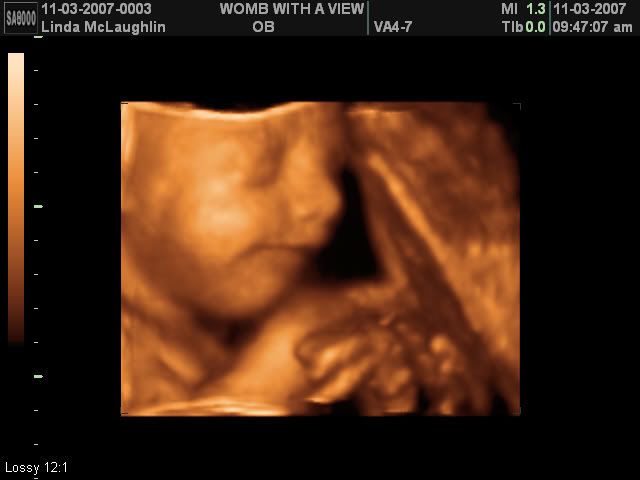

I guess the first thing to start off with is my surprise for M&M a few weeks ago. I got them a 3-d ultrasound session! It was so much fun! We have confirmed she is 100% girl :-) Unfortunately, Miss Baby M wanted nothing to do with picture taking that day so the ultrasound tech had to keep jiggling my belly to get her to turn around - haha!

Anyway, here's a few pictures of M&M's beautiful baby girl <3

Isn't she beautiful? I can't wait to see her in person to see how much she looks like the pictures. <3